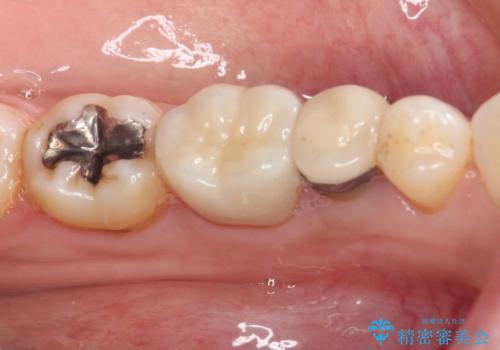

- 奥歯の銀歯をセラミックの白い歯にして、しみる症状も改善したいとのことで来院された患者様です。

知覚過敏の症状が強い歯と、銀歯の範囲や銀歯の下のむし歯が大きい歯は、インレー修復では対応が難しいためオールセラミッククラウンで、インレー修復で対応が可能な歯ではセラミックインレーにて修復することとしました。